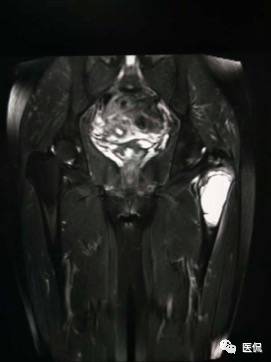

患者资料:男,26岁,左髋部疼痛10余天,无明显诱因出现左侧髋部疼痛,影像行走,夜间疼痛尤其明显。

影像资料:

(3)MRI ABC的特征为鼓囊状的膨胀性破坏,呈单囊或由低信号的间隔分隔成大小不等的多囊。因血细胞和血浆的分离和沉淀,囊内可见液-液平面。在T2WI上,液面上层为高信号,下层为低信号;T1WI上则相反,上层为低信号,下层为偏高信号。液-液平面是ABC较特征的征象。增强检查低信号的纤维间隔呈环形强化。继发性动脉瘤样骨囊肿可在其原发病灶内有液-液平。

【诊断要点】发生于青少年长骨干骺端偏心膨胀的溶骨性病变,MRI检查病灶内见有液-液平征象时应首先考虑为动脉瘤样骨囊肿。